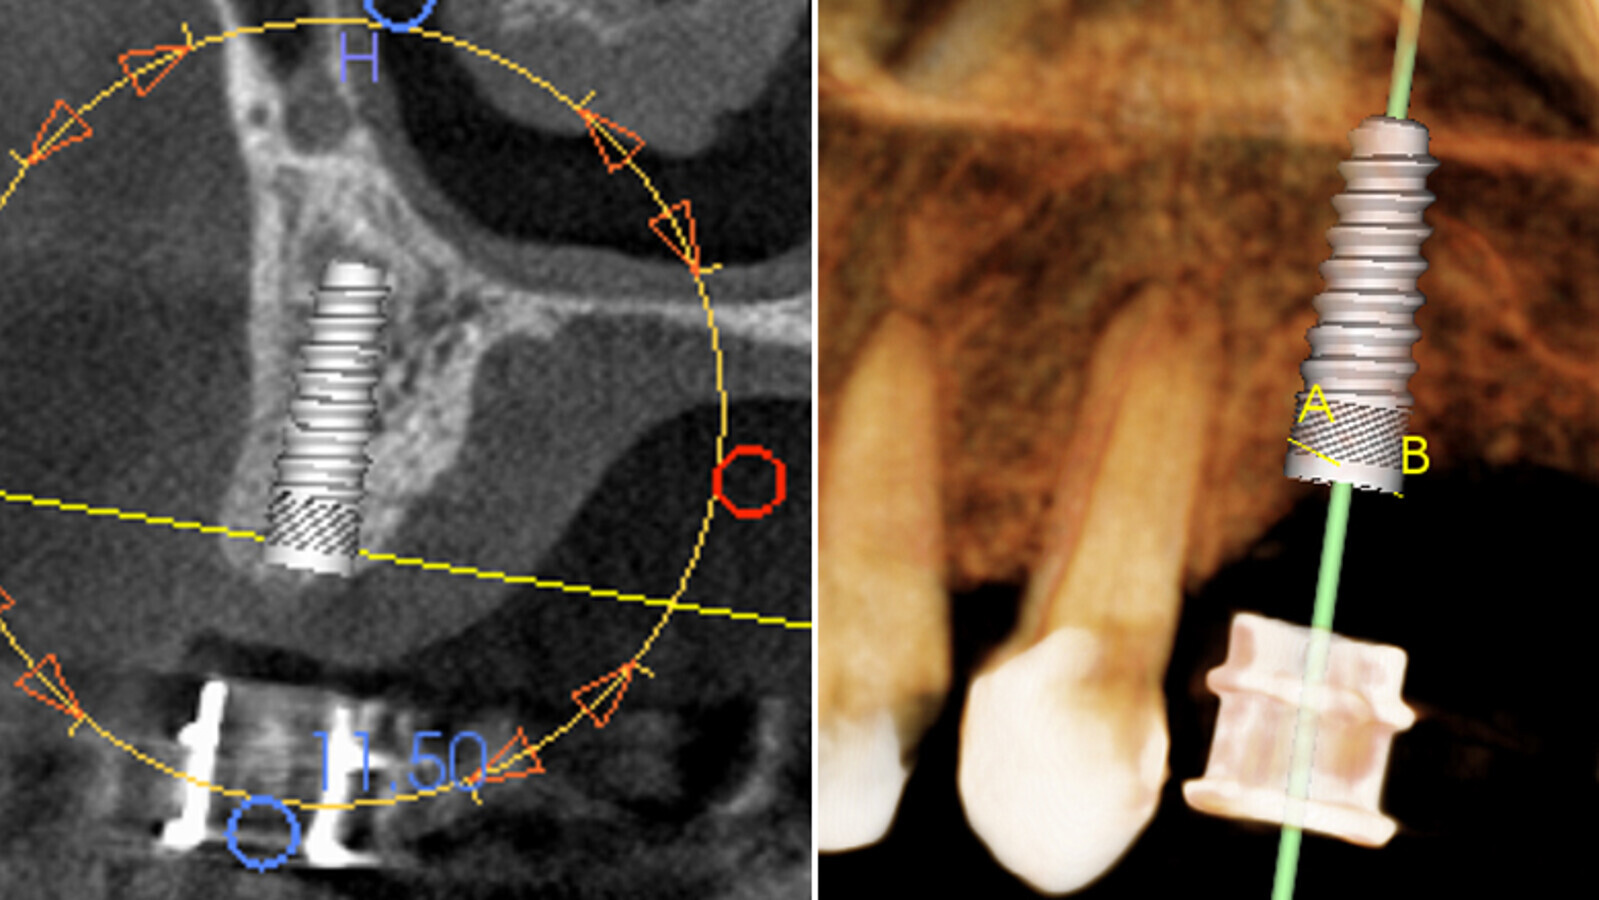

Figuras 4a, 4b. Con la información proporcionada por la tomografía Cone Beam, realizamos la planificación virtual del implante, angulación e inserción ósea, utilizando el software del propio tomógrafo.

Figuras 7a, 7b PRE Qx. En la tomografía Cone Beam pre-quirúrgica se observa la planificación digital del implante en cuanto a su angulación, dirección y posicionamiento.

Figuras 7a, 7b POST Qx. En la tomografía post-quirúrgica se evidencia el implante ya colocado en boca de igual forma a cómo se realizó en la planificación inicial, lo que confirma que esta técnica muy efectiva para el especialista, y que además minimiza riesgos.